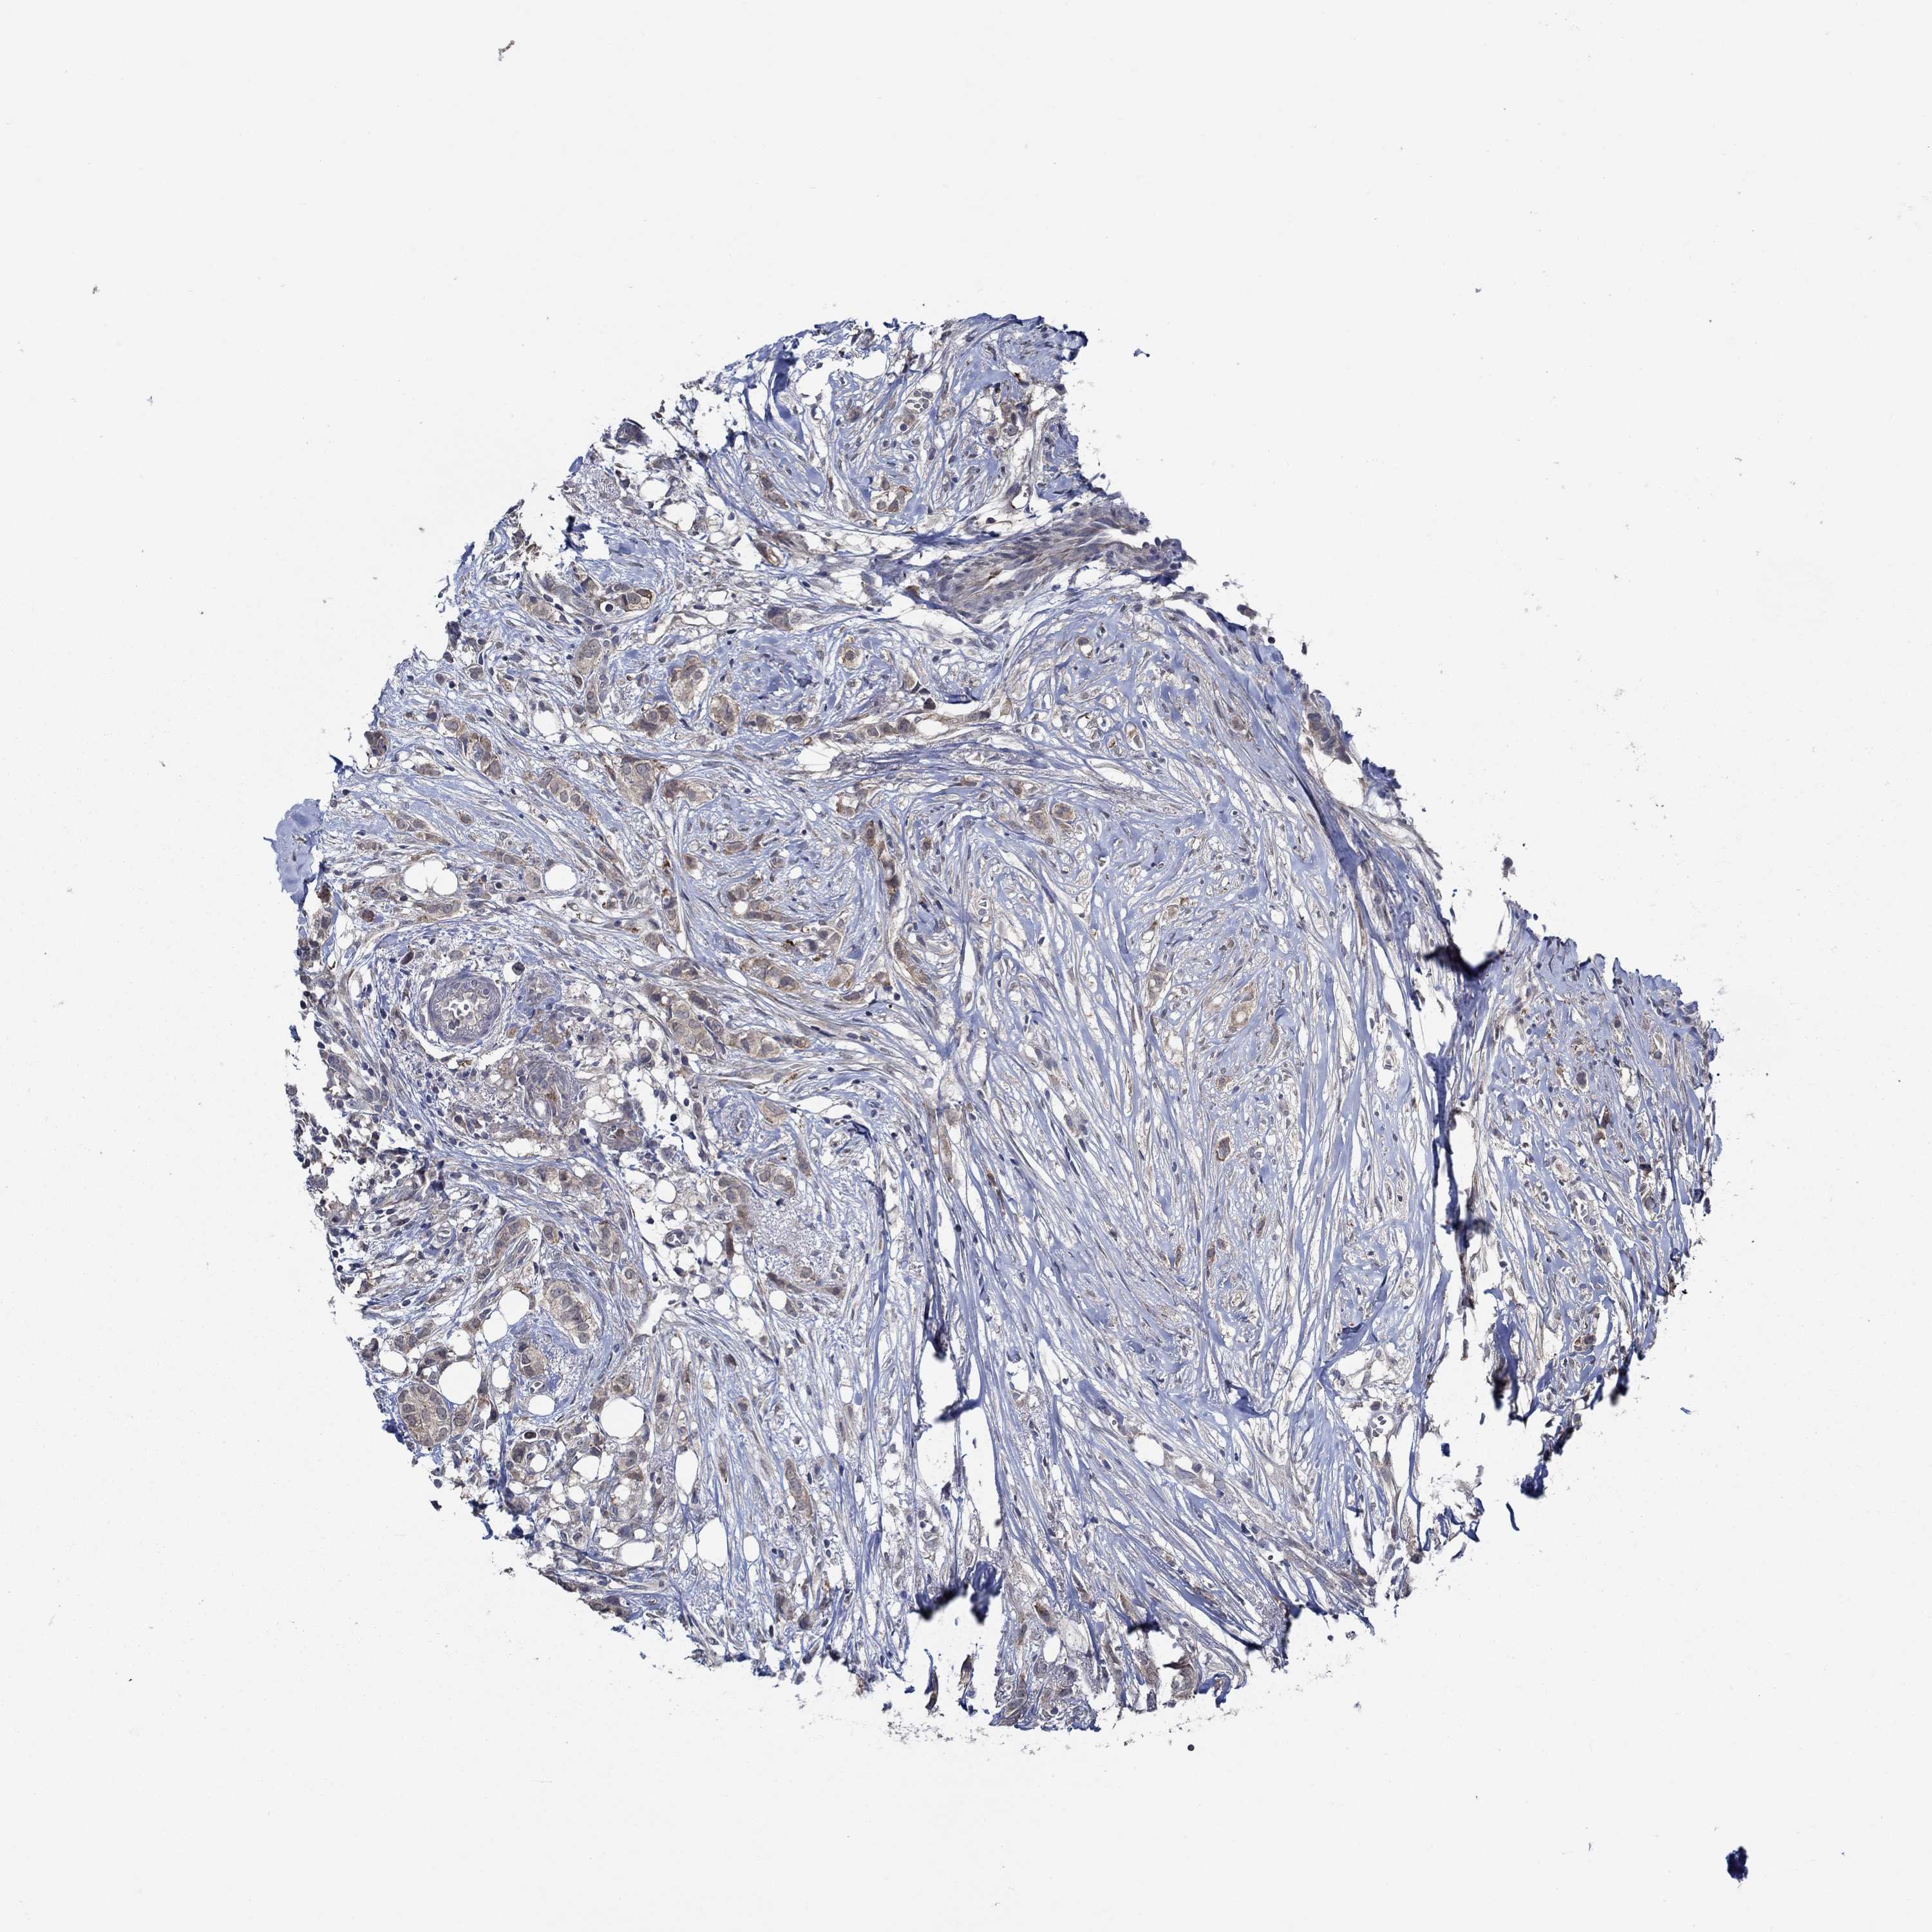

BRCA TCGA BRCA VALIDATION PROTEIN EXPRESSION

ANTIBODIES

AND

VALIDATION